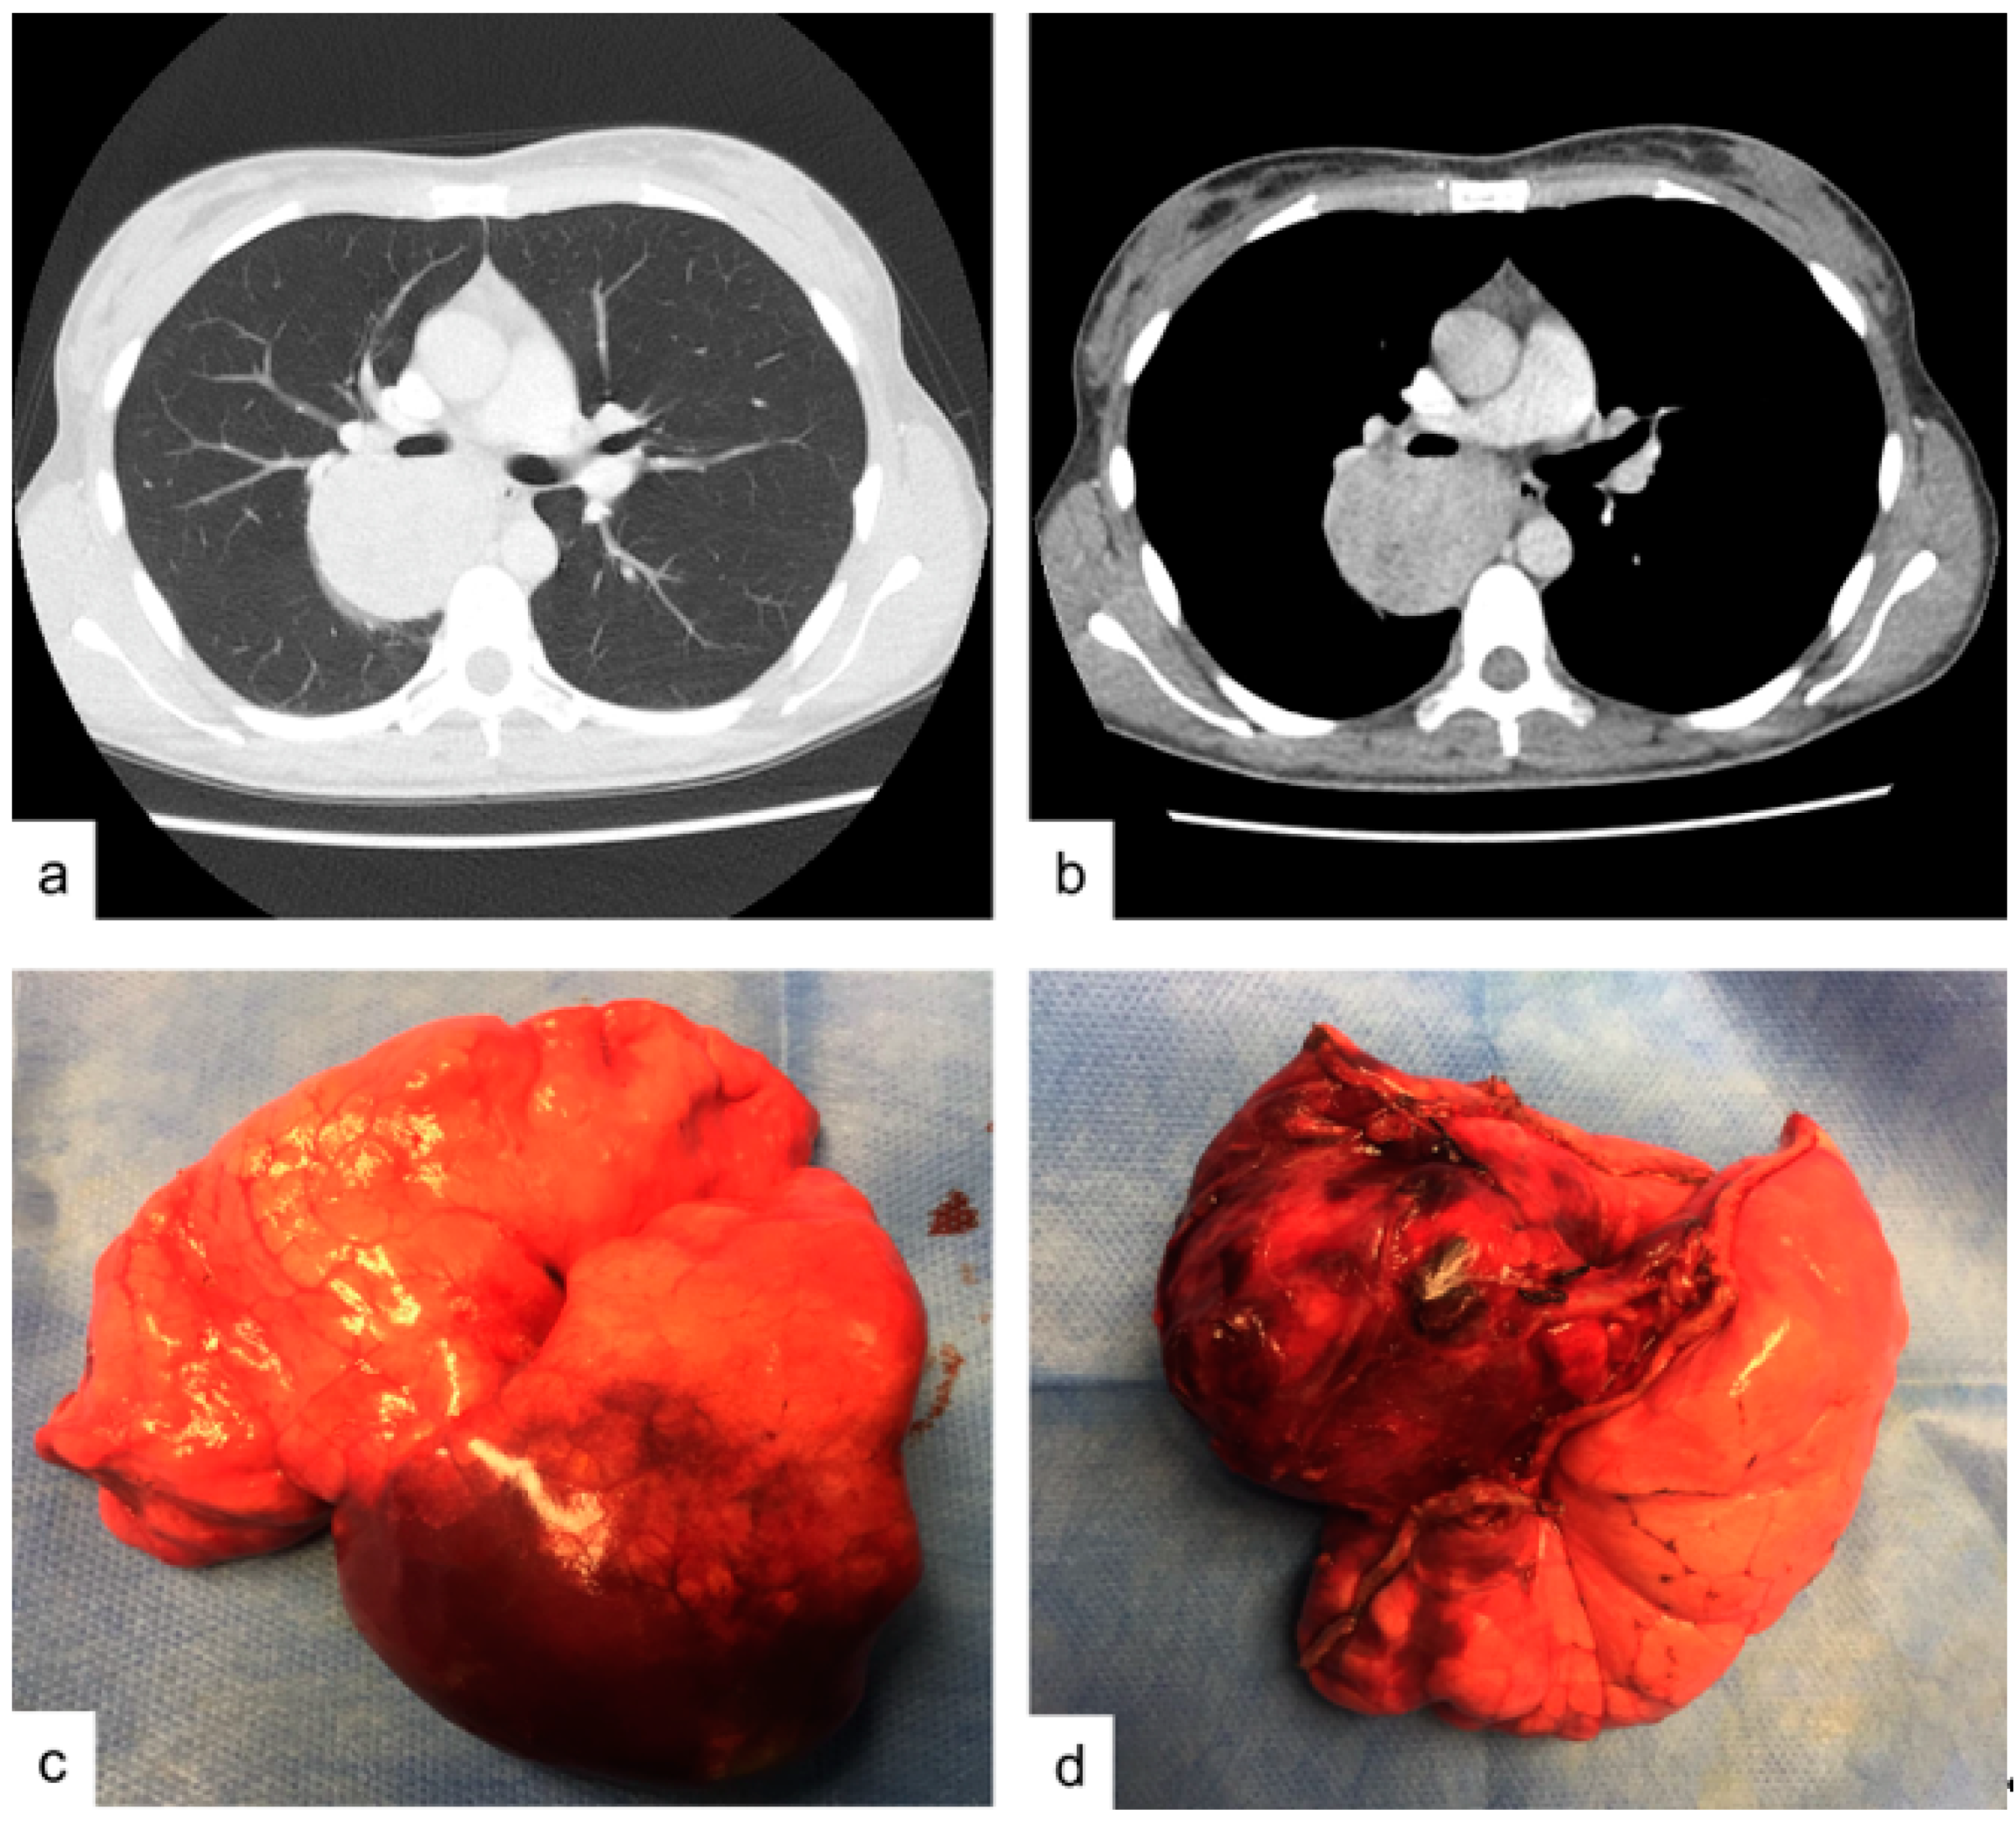

A 38-year-old woman presented to the Emergency Department of our Hospital with rectorrhagia of uncertain origin and anemia. The patient denied hemoptysis, dyspnea, fever and weight loss. She had never smoked. Colonoscopy showed diffuse polyposis throughout the bowel. While performing routine pre-procedural analysis before colonoscopy, chest X-rays showed a huge abnormal mass occupying the right upper pulmonary lobe. Contrast-enhanced chest CT scan showed a well-defined, hypodense soft-tissue lesion measuring 50 by 65 mm, located in the posterior segment of the right upper lobe and upper segment of the right lower lobe, in contiguity with the adjacent mediastinal pleura (Figure 1a,b). Positron emission tomography PET/CT scan revealed slight fluorine-18 deoxyglucose (FDG) uptake within the lesion (SUV max: 3.5). Endobronchial ultrasound-guided transbronchial needle aspiration (EBUS-TBNA) was performed using a 22 G aspiration needle (Vizishot®, Olympus, Japan). The cytologic preparation showed epithelial clusters of monomorphic cells with focal atypia in an adenomorphic and papillary pattern, without mitosis. These findings were highly suggestive of a neuroendocrine pulmonary tumor. However, immunohistochemistry revealed positive staining for CK-7 and TTF-1, while common neuroendocrine markers such as chromogranin A and synaptophysin were negative, excluding the diagnosis of a carcinoid tumor. The Proliferative index, evaluated by Ki67+, was <2–3%. The final cytological report supported a diagnosis of lung adenocarcinoma (shown in Figure 2a,b). For this reason, the patient underwent surgery: through a lateral right thoracotomy, right upper lobectomy plus lower lobe upper segmentectomy (due to the suspicion of transfissural invasion) were performed.

Figure 1.

Case 1. (a,b) contrast enhanced chest CT-scan showing an hypodense soft-tissue lesion in the size of mm 50 by 65 mm located between the posterior segment of the right upper lobe and lower lobe upper segment. (c,d) operative specimen: right upper lobe and lower lobe upper segment after surgical excision.

2.1. Macroscopic Findings.

The resected specimen contained a yellowish tumor, easily enucleable, with central necrosis, measuring 5.5 by 5.0 cm in diameter (Figure 1c,d). The tumor markedly expanded the lungs, was encapsulated, peripheral and subpleural.